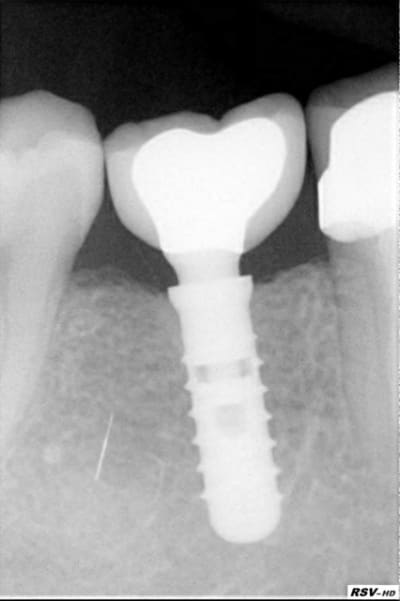

pose d'un axiom en 4*12 en juillet en sous crestal comme il le faut.

et aujourd'hui raido début de cratérisation : petite mais existante;

vu aujourd'hui lors de la mise en place vis de cicat petite operculisation de la vis de couv en palatin (discrète mais existante) donc ouverture nettoyage et mise en place de la vis de cicat .

la forme de cette vis de cicat ne serait elle pas un chouilla agressive pour le TC ? votre avis les poseurs ?

pour la forme et le fond pano avant retro à la pose et rétro aujourd'hui